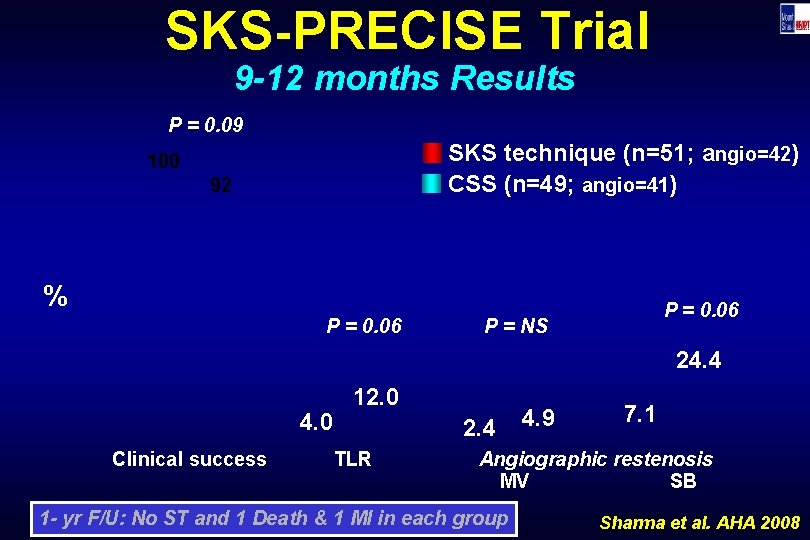

SKS-PRECISE Trial 9 -12 months Results P = 0. 09 SKS technique (n=51; angio=42) CSS (n=49; angio=41) 100 92 % P = 0. 06 P = NS 24. 4 4. 0 Clinical success 12. 0 2. 4 TLR 4. 9 7. 1 Angiographic restenosis MV SB 1 - yr F/U: No ST and 1 Death & 1 MI in each group Sharma et al. AHA 2008